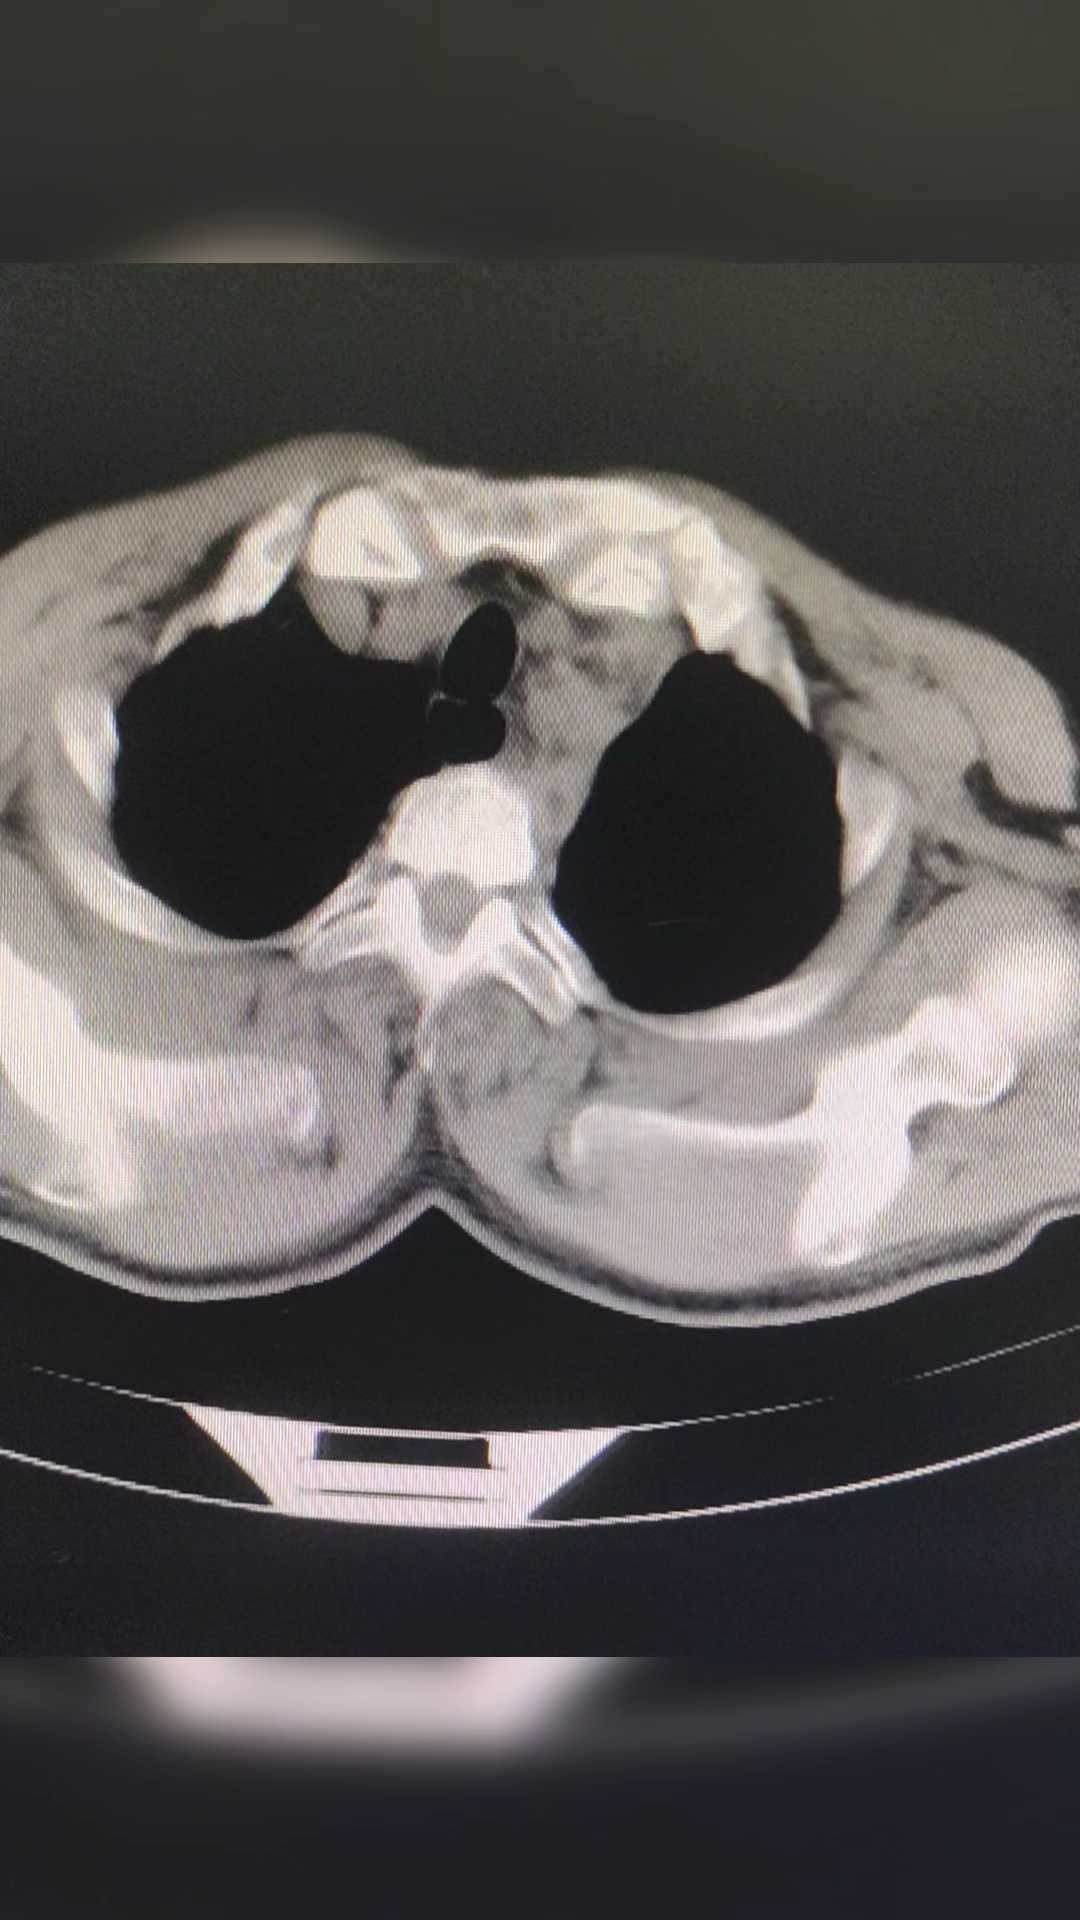

看过CT,园友们能看出是什么病吗?

主动脉夹层!

这个结果,是不是有点意外?因为症状不典型,如果不查CT,只按心脏的问题处理,那就麻烦大了!

急性 主动脉夹层 最典型症状为突发性剧烈胸/背疼痛,通常会伴有低血压和休克,其他特征性临床表现为心包积液、主动脉瓣反流和冠状动脉受累等。但是这个患者的胸痛不是很重,也没有低血压,双上肢的血压也没有明显的差距!特征性的表现,也就是心包积液了!